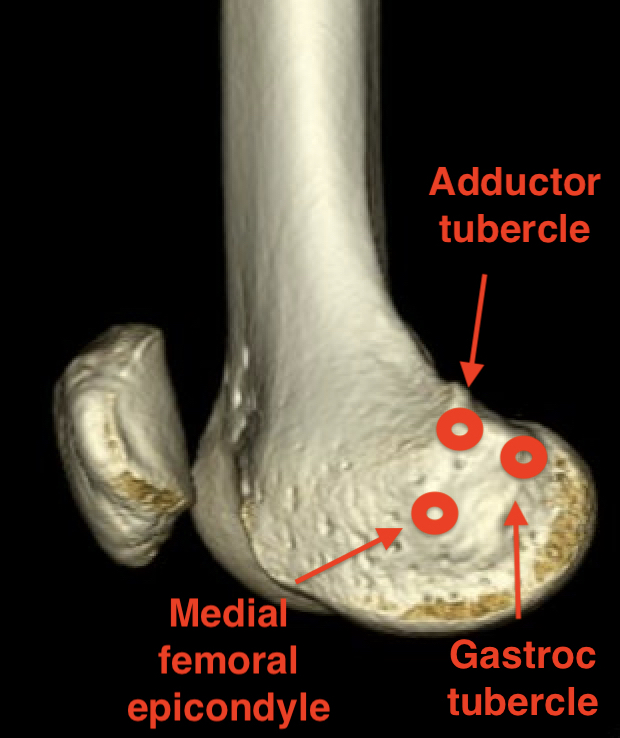

Origin

- medial femoral condyle

- between medial femoral epicondyle and adductor tubercle

- superior to origin of MCL

Insertion

- superomedial patella

- broad insertion 2 - 3 cm